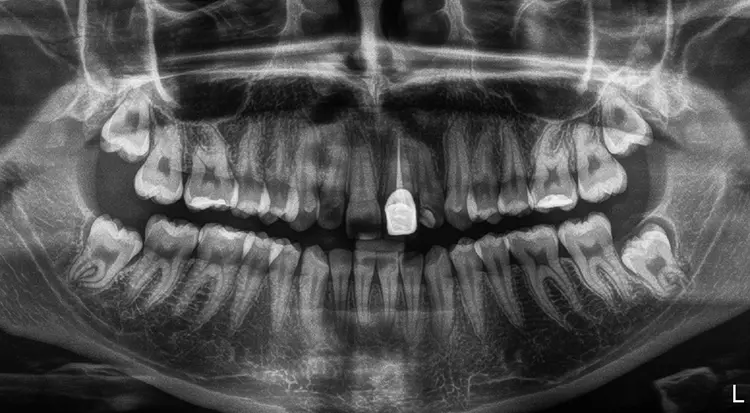

Im Rahmen des Erstgespräches berichtete die junge Patientin von einem Sturzereignis, bei dem der Schneidezahn frakturierte. Ihr damaliger Zahnarzt führte eine Wurzelkanalbehandlung durch und versorgte den Zahn mit einer Krone aus Lithiumdisilikat. Das anfänglich sehr ansprechende ästhetische Behandlungsergebnis hätte sich jedoch nach der Eingliederung mit der Zeit verändert und die Patientin stellte eine zunehmende Verfärbung der Frontzahnkrone fest (Abb. 2 und 3).

Dies kann aus einer nachträglich eingetretenen Verfärbung des devitalen Zahnes resultieren. Durch die sehr hohe Transluzenz der Glasphase einer Lithiumdisilikat-Restauration kann die dunkle Stumpffarbe durchschlagen und zu einem ästhetisch störenden „Grauschleier“ führen. In einem intensiven Beratungs- und Aufklärungsgespräch wurden der Patientin die Schwierigkeiten und Herausforderungen einer Einzelzahnkrone in der ästhetischen Zone bei einer hohen Lachlinie mit Exposition der Gingiva dargestellt.

Die vorgefundene Präparation konnte im labialen Bereich in 3 Ebenen anatomisch reduziert und optimiert werden. Bei der Platzierung des zirkulären Präparationsrandes war die „biologische Breite“ nicht berücksichtigt worden und der Kronenrand lag deutlich subgingival.

Materialauswahl

Die Auswahl des Materials für die definitive Krone wurde in Rücksprache mit dem Zahntechniker getroffen. Sie erfolgte nach der Herstellung der Arbeitsmodelle, der Beurteilung der Platzverhältnisse, der Stumpffarbe und der definierten Zielfarbe. Aufgrund des verfärbten und devitalen Zahnes und zur Vermeidung des „Grauschleiers“ galt es, ein Material mit weniger Transluzenz als Lithiumdisilikat zu verwenden.

Es sollte ein Zirkonoxidmaterial mit hochästhetischen Eigenschaften zum Einsatz kommen. Die Wahl fiel auf IPS e.max ZirCAD Prime, ein Werkstoff der zwei Zirkoniumdioxid-Rohstoffe kombiniert: im Dentinbereich ein 3Y-TZP-Zirkonia mit hoher Festigkeit (1.200 MPa Biegefestigkeit) und im Schneidebereich ein transluzenteres 5Y-TZP-Zirkonia (650 MPa Biegefestigkeit). Der stufenlose Farb- und Transluzenzverlauf in den Materialscheiben ist ein zusätzlicher Vorteil für derartige Restaurationen im sichtbaren Bereich.